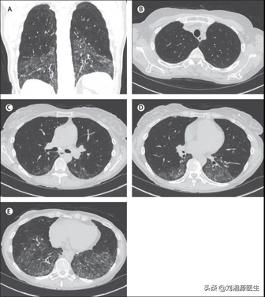

25.系统性硬化症相关间质性肺病有哪些影像学特点?答:高分辨CT上最常见的影像学表现是非特异性间质性肺炎,在80%以上的患者中可见(图13 A-E)。特征是成片状磨玻璃样改变,尤以胸膜下区域明显。在系统性硬化症相关间质性肺病患者中,只有10%的患者存在明确的间质性肺炎模式,没有磨玻璃样变但伴蜂窝样变。

图13 A~E系统性硬化症相关 间质性肺病的高分辨CT影像